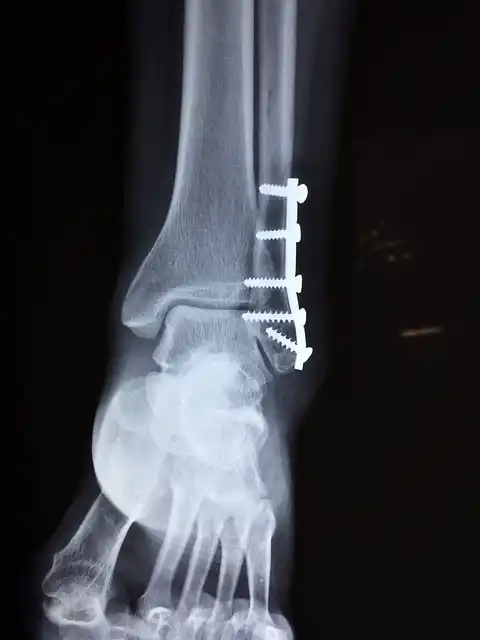

b. 발목 골절

과도한 체중은 발목 골절과 같은 더 심각한 부상으로 이어질 수 있습니다. 발목은 체중 증가에 따라 심각한 영향을 받을 수 있는 복잡한 관절입니다. 이 부위의 골절은 고통스러울 수 있고 수술적인 중재가 필요할 수 있습니다.